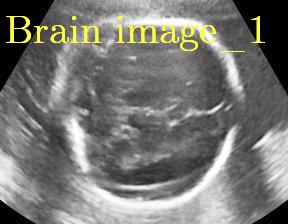

We propose a novel method based on convolutional neural networks (CNNs) to automatically estimate pixel-wise confidence maps of acoustic shadows in 2D US images. Our method learns an initial latent space of shadow regions from images consisting of multiple anatomies and with global image-level labels (“has shadow” and “shadow-free”), e.g. Fig. 1(a). The basic latent space is then estimated by learning from fewer images of a single anatomy (fetal brain) with coarse pixel-wise shadow annotations (approximately of the images with global image-level labels), e.g. Fig. 1(b). The resulting latent space is then refined by learning shadow intensity distributions using fetal brain images so that the latent space is suitable for confidence estimation of shadow regions. By using shadow intensity information, our method can detect more shadow regions than the coarse manual segmentation, especially relatively weak shadow regions.

We propose a shadow-seg module to extract generalized shadow features for a large range of shadow types in fetal US images under limited weak manual annotations. Since shadow regions have different shapes, various intensity distributions and uncertain edges, the pixel-wise annotation of shadow regions is time consuming and relies heavily on annotator’s experience (e.g. various annotations in Fig. 1(b)). This generally results in manual annotations of limited quantity and quality. Compared with pixel-wise shadow annotations, global image-level labels (“has shadow” and “shadow-free” in our case) are easier to obtain, and shadow images with global image-level labels can contain a larger variety of shadow types. Therefore, we use a shadow-seg module that combines unreliable pixel-wise annotations and global image-level labels as weak annotations.The proposed shadow-seg module contains two tasks, (1) shadow/shadow-free classification using image-level labels, and (2) shadow segmentation that uses few coarse pixel-wise manual annotations ( of the global image-level labels). Shadow features can be extracted during simple shadow/shadow-free classification and subsequently optimized for the more challenging shadow segmentation task. In our case, shadow features extracted by the classification network cover various shadow types in a range of anatomical structures. These shadow features become suitable for the shadow segmentation after being optimized by a shadow segmentation network.

This data set comprises 643 fetal brain images and has no overlap with the multi-class data set. Shadow regions in this data set have been coarsely segmented by two bio-engineering students using trapezoid-shaped segmentation masks for individual shadow regions.